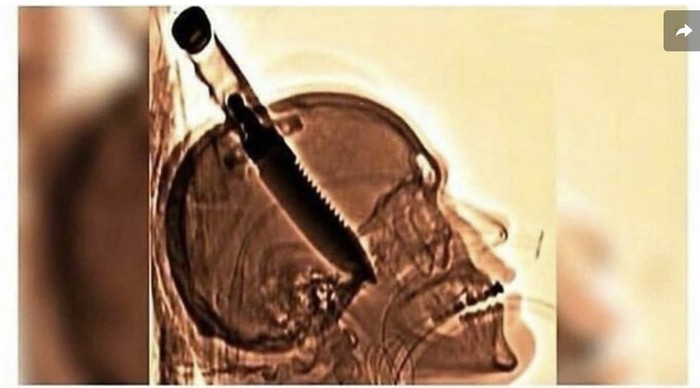

Pada tahun 1998, Michael Hill ditikam di tengkoraknya, oleh orang tak dikenal, dengan pisau besar untuk bertahan hidup ketika dia membukakan pintu di rumah temannya. Dia bertahan hidup bahkan tanpa infeksi dan mendapatkan kembali kesadaran dan seluruh fungsi tubuhnya dalam waktu seminggu, meskipun pisau tersebut telah menyebabkan kerusakan permanen pada ingatannya dan melumpuhkan tangan kirinya. Foto: Instagram/@horrorsfs